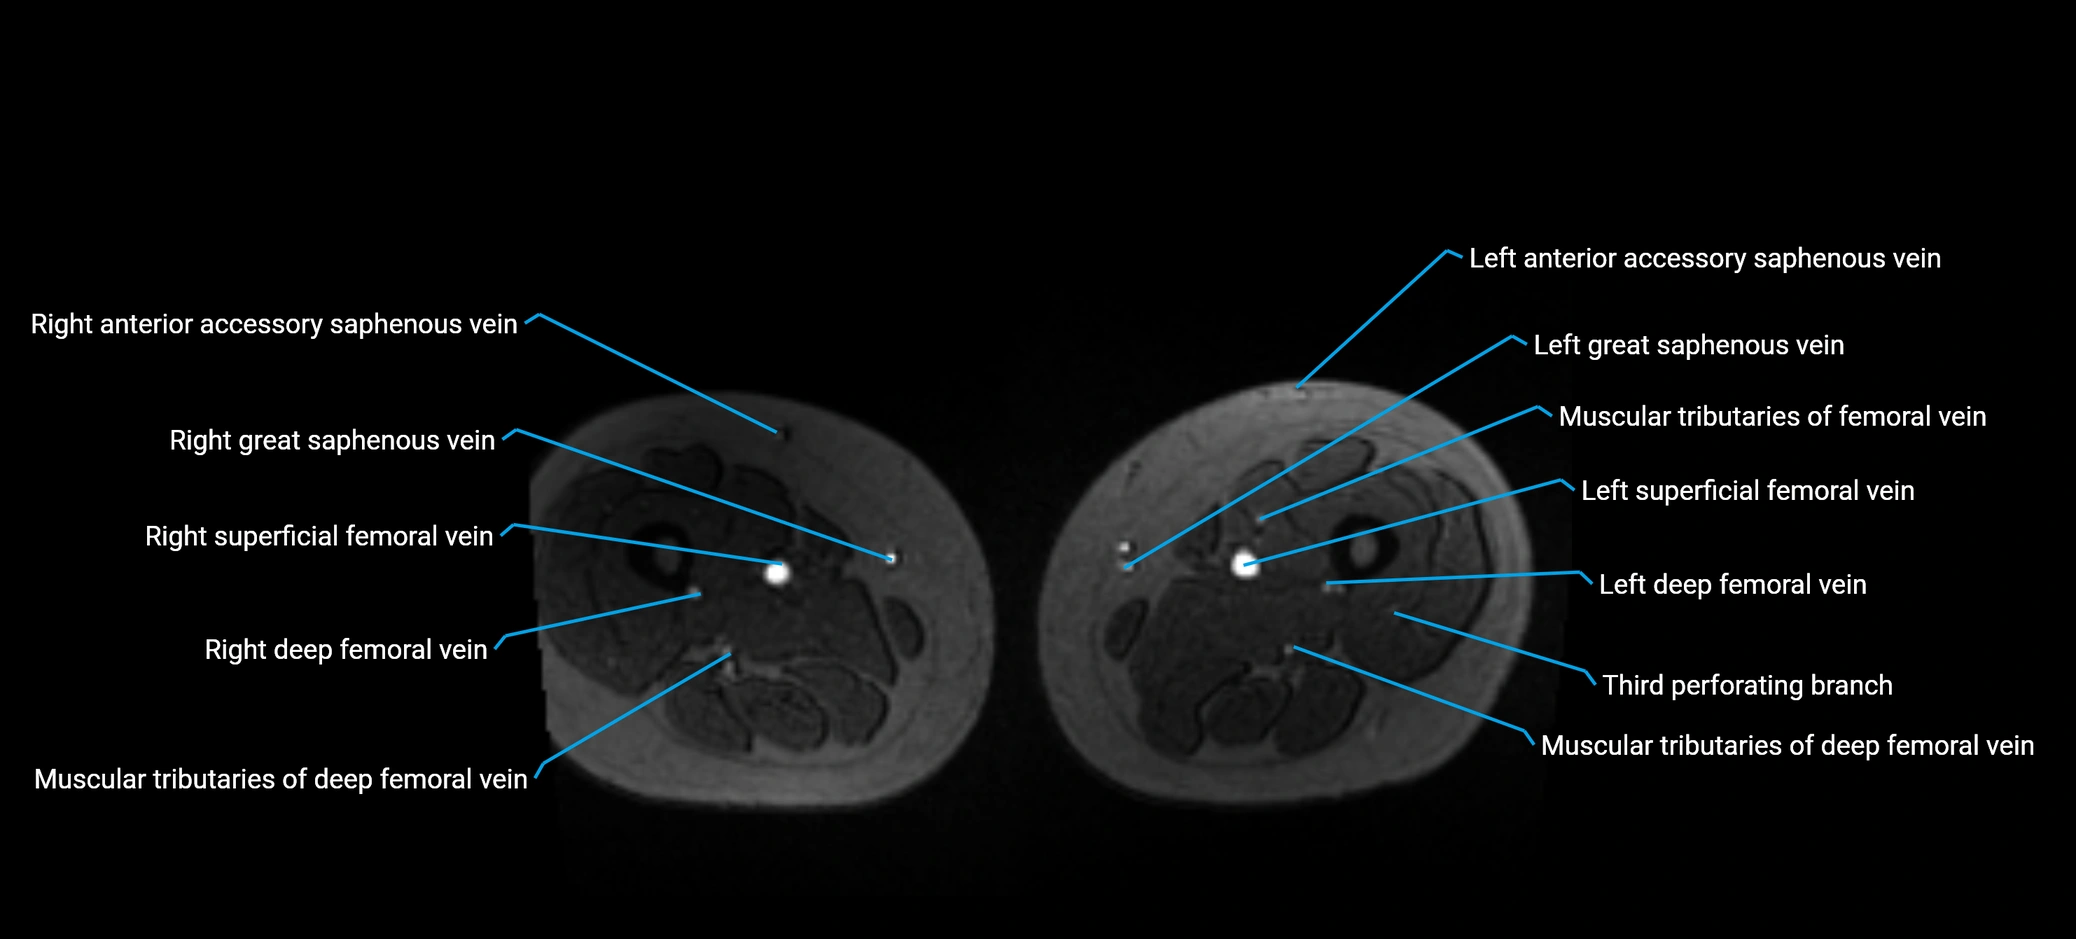

MRI image

image